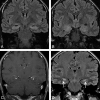

Results: Thirty-three of 42 patients (78.6%) demonstrated enlargement and T2 hyperintensity of mesial temporal lobe structures at some time point. Mesial temporal sclerosis was commonly identified (16/33, 48.5%) at follow-up imaging. Six of 9 patients (66.7%, P = .11) initially demonstrating hippocampal enhancement and 8/13 (61.5%, P = .013) showing hippocampal restricted diffusion progressed to mesial temporal sclerosis. Conversely, in 6 of 33 patients, abnormal imaging findings resolved.

Conclusions: Autoimmune voltage-gated potassium channel complex encephalitis is frequently manifested as enlargement, T2 hyperintensity, enhancement, and restricted diffusion of the mesial temporal lobe structures in the acute phase. Recognition of these typical imaging findings may help prompt serologic diagnosis, preventing unnecessary invasive procedures and facilitating early institution of immunotherapy. Serial MR imaging may demonstrate resolution or progression of radiologic changes, including development of changes involving the contralateral side and frequent development of mesial temporal sclerosis.